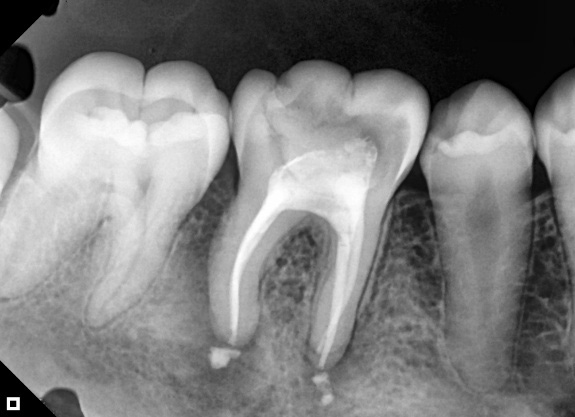

A 25-year-old female patient was referred to the Endodontics Specialization course at the Escola Educação Inteligente – Uningá (Londrina, Paraná, Brazil) for evaluation and endodontic treatment of tooth 46 (lower right first molar). Clinical and radiographic examinations (periapical radiography) were performed, as well as anamnesis, and a coronary opening was found. The tooth was asymptomatic at the time, and the periapical lesion on element 46 was clearly visible with radiography (Figure 1), indicating pulp necrosis.

Figure 1: Initial situation